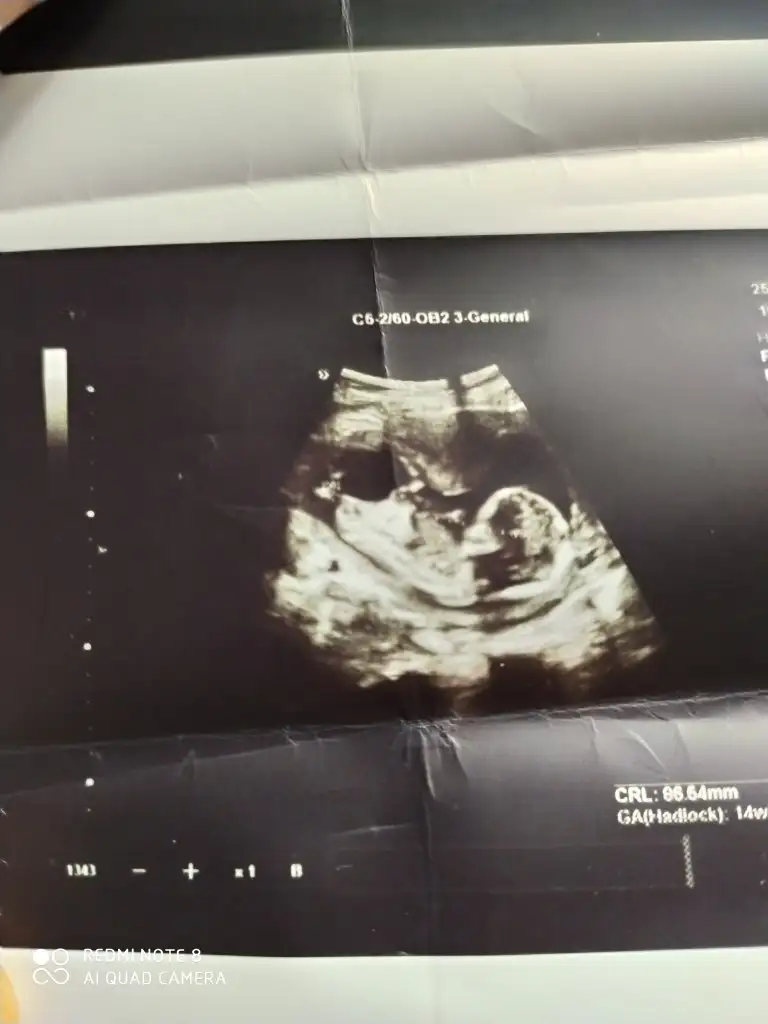

Ben de kız demistim .o haftalik ultrason kaginda daha belli oluyor cinciyet tahmini.çıkınti paralel oldugu icin kız demistim ben de.buradaki fotoda net belli sizin.seni çok iyi anlıyorum.benim de iki kızım var.ve ücuncuyu istiyoruz.olmadi 5 aydir gebelik.hayırlısı olsun.saglikli olsun en önemlisi.Rabbimin vardır bildiği .verdiyse en hayırlısını vermistir.gönlünü ferah tut .Evet Dr söyledi teşekkürlerEki Görüntüle 2764435

Ama çoğu kişi erkek bu bebek diyorBen de kız demistim .o haftalik ultrason kaginda daha belli oluyor cinciyet tahmini.çıkınti paralel oldugu icin kız demistim ben de.buradaki fotoda net belli sizin.seni çok iyi anlıyorum.benim de iki kızım var.ve ücuncuyu istiyoruz.olmadi 5 aydir gebelik.hayırlısı olsun.saglikli olsun en önemlisi.Rabbimin vardır bildiği .verdiyse en hayırlısını vermistir.gönlünü ferah tut .

Ben cizmedim isegramdan bu sayfa çizdi cinsiyetini öğren diye bi sayfaSen ustunu cizmissin bilemedim simdi.baska bir dr a da gitsen imkanın vaktin varsa için rahat olur .

Evet o sayfa bana erkek dedi bugün öğrenmeye gideceğim bende hayırlısı olsunBen cizmedim isegramdan bu sayfa çizdi cinsiyetini öğren diye bi sayfa